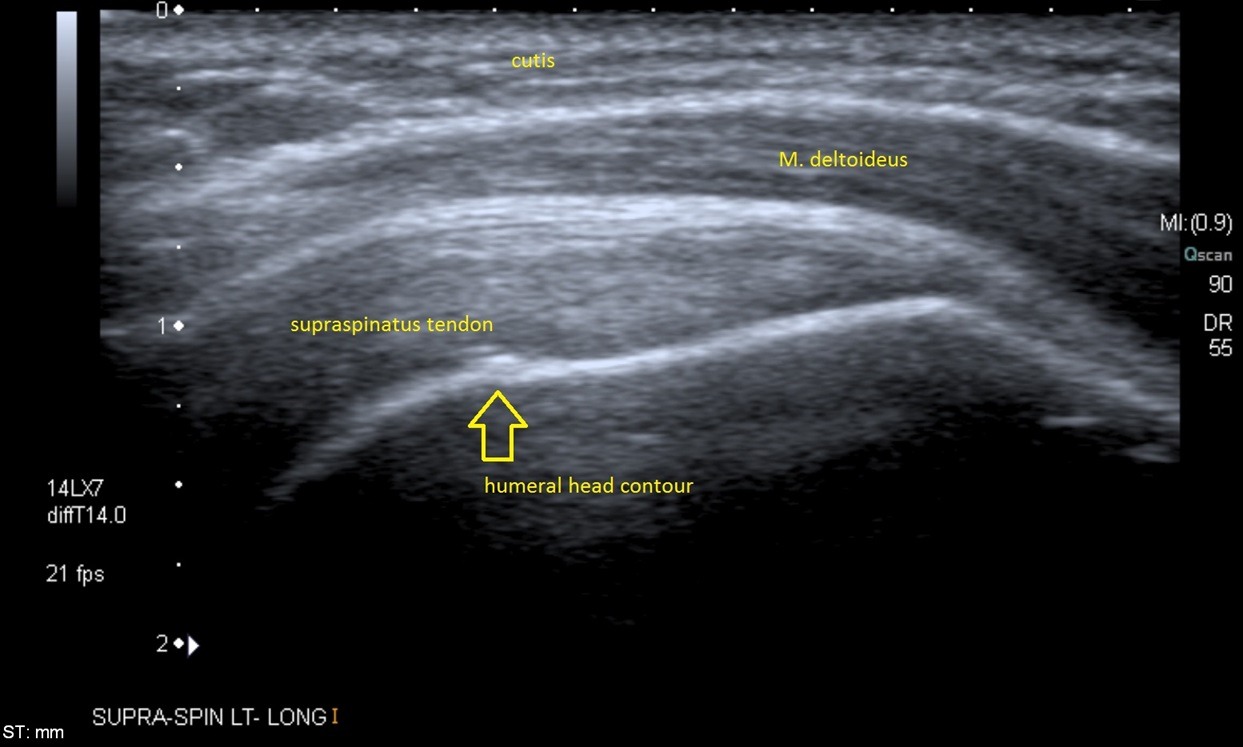

Ultrasound imaging is a quick and accurate way of assessing common musculoskeletal (MSK) conditions like tendon and ligament injuries.

- Tendon tears or tendonitis of the rotator cuff in the shoulder, Achilles tendon in the ankle, patellar tendonitis at the knee, tennis and golferβs elbow and many other tendons throughout the body

Ultrasound imaging produces pictures of the inside of the body, and is also known as ultrasound scanning or sonography. It is safe and painless procedure that utilises high-frequency sound waves to create real-time images of the muscles, tenons, ligaments, joints, nerves and soft tissues throughout the body.